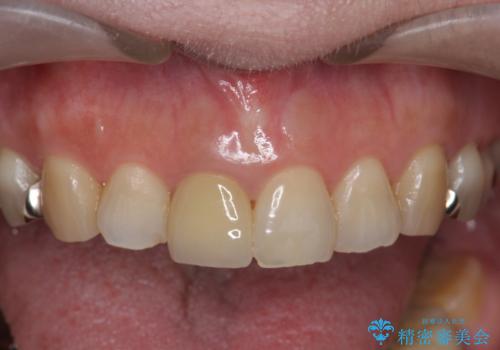

近年前歯のクラウン製作に用いられるジルコニアクラウンは、金属を用いていないため経年的に歯ぐきの位置が変わっても黒いラインが見えることなく審美性の意地が期待できます。